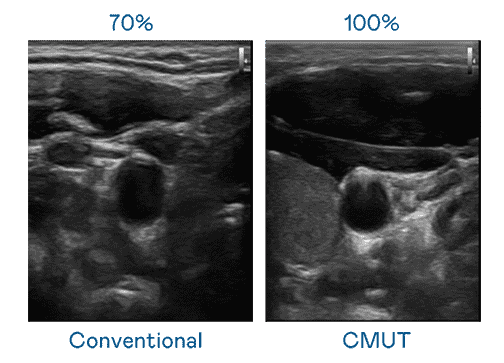

CMUT 技术是一种用电容式微机电元件来产生超音波讯号的技术。。。与传统 PZT 压电式技术相比,,,CMUT 频宽增加 30%,,,,更宽频的超音波讯号让影像解析度大幅提升,,是实现高影像品质医疗超音波扫描、、、、促进精准医疗发展的关键技术。。

大频宽带来超清晰影像

超音波影像的解析度高低,,首先取决于探头能发出的讯号频宽。。888.BY集团电子游戏 CMUT 可提供高清晰的超音波讯号,,提供高频宽、、、高灵敏度、、、、影像纹理细节更高的超音波影像,,,,协助医护人员缩短影像判读时间及利用精准的医疗影像进行诊断。。。。